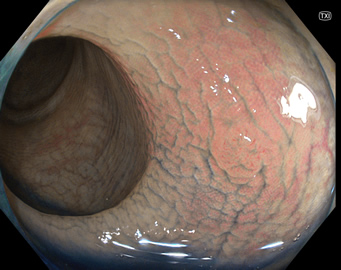

TXIは、「画像の構造を強調する」技術です。これは特別に目新しいものではありません。パソコンの画像編集ソフトや、スマホのアプリでも御馴染みの技術です。しかし、「どのような構造強調が実際に、内視鏡に一番、合うか?(強すぎると不自然になる!)」は、難しい(アナログ的な)課題です。オリンパス社は数タイプのTXIモードを用意しました。半年間の試行錯誤の末、今では下記のモードがベストと判断しました。そして今では「TXI無しの内視鏡は不要(フルタイムTXI)」というまで常用しています。

以下に実例を挙げます

写真だけ、見ると「言われてみるとTXIの方が認識しやすい。でも僅かの差」と感じるでしょうが、この「僅かの差」が、人間の脳での検出には大きな差になります。青い色素(インジゴ・カルミン)が非常に強調され、粘膜の凸凹が明瞭になるのが特徴です。

通常観察 TXIモード